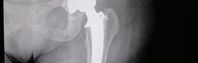

Ortopedie a manuální medicína